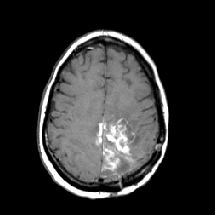

Noise removal: Gaussian filter is a well-known method and is used to smooth a noise by taking the average values surrounding a noise kumar2017noise . In this experiment, the noise removal is performed using a Gaussian filter. Essentially, a Gaussian filter is a low pass filter that is non-uniform. Also, the kernel is symmetric in a Gaussian filter, which can reduce direction bias, if any. Application of a Gaussian filter requires convolution of 2D Gaussian distribution (see Eqn. 2) given an image input. It may be noted that 2D Gaussian distribution is the product of two 1D Gaussian functions (see Eqn. 1). The kernel coefficients are sampled from Eqn. 2. An example showing the noisy image and the same after the removal of noise is shown in Fig. 3.

Refer to caption

Figure 3: Example of noisy MR image and the image after noise removal.